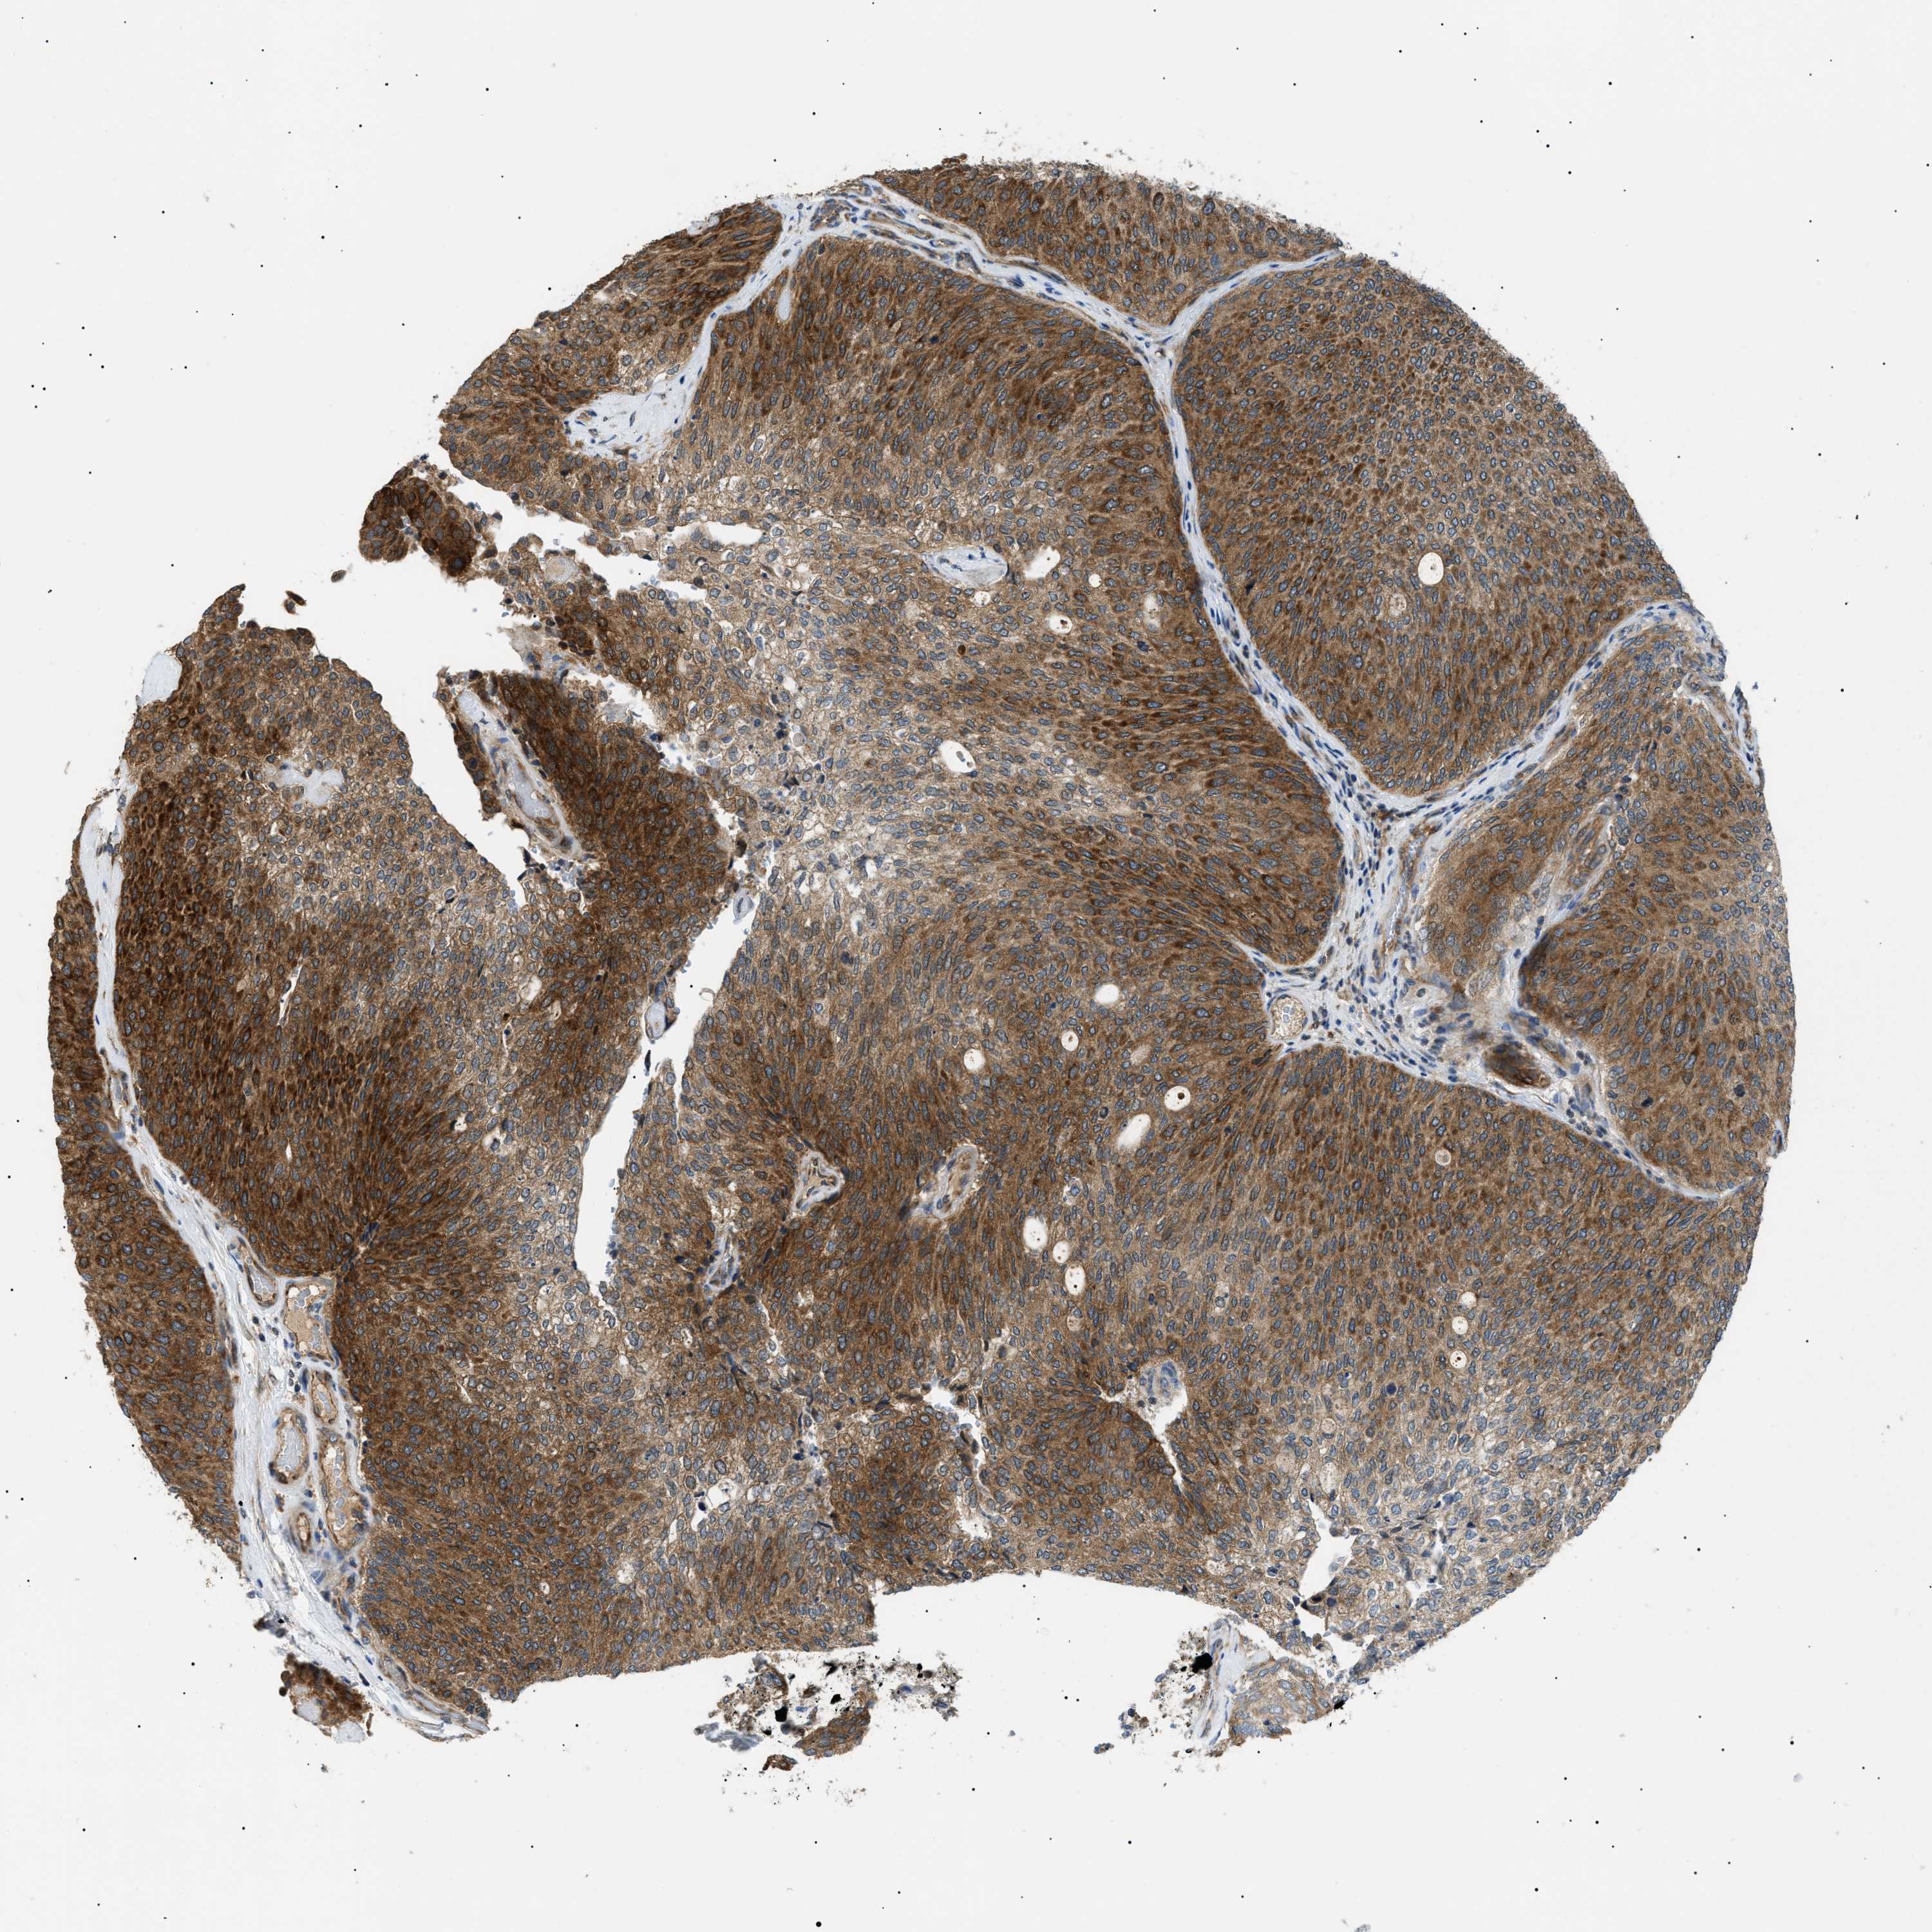

UROTHELIAL CANCER - Protein expressioni

A mouse-over function shows sample information and annotation data. Click on an image to view it in a full screen mode. Samples can be filtered based on level of antibody staining by selecting one or several of the following categories: high, medium, low and not detected. The assay and annotation is described here.

Note that samples used for immunohistochemistry by the Human Protein Atlas do not correspond to samples in the TCGA dataset.

Antibody stainingi

Antibody staining in the annotated cell types in the current human tissue is reported as not detected, low, medium, or high, based on conventional immunohistochemistry profiling in selected tissues. This score is based on the combination of the staining intensity and fraction of stained cells.

Each image is clickable and will lead to virtual microscopy that enables deeper exploration of all samples and also displays staining intensity scores, fraction scores and subcellular localization as well as patient and tissue information for each sample.

Antibody HPA016431

Staining

High

Medium

Low

Not detected

Intensity

Strong

Moderate

Weak

Negative

Quantity

>75%

75%-25%

<25%

None

Location

Nuclear

Cytoplasmic/membranous

Cytoplasmic/membranous,nuclear

Urothelial carcinoma, Low grade

Urothelial carcinoma, High grade